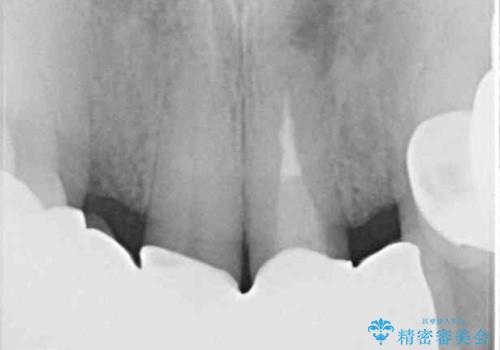

- ブリッジと歯肉の隙間にものが挟まったり空気が抜けたり、歯肉ラインの黒い縁が目立ってしまったりと、前歯のブリッジの作り直しを希望して来院された患者様です。

自然な仕上がりとするため、金属を使用しないオールセラミックブリッジにより補綴治療を行うこととしました。

露出していた歯根や金属の縁が見えてしまい、なかなか口を開けて笑うことができなかったのですが、歯肉の位置に縁を合わせることで自然な仕上がりとなりました。